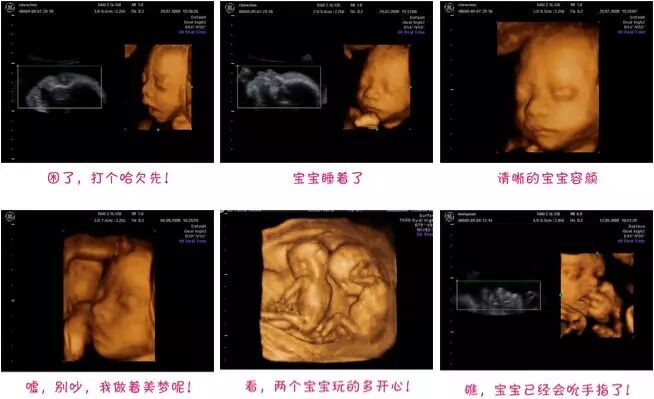

鲁医生告诉医馆君,其实他们医生这里没有‘四维’的说法,准确的说法应该是“实时三维”。因为所谓的“四维”,就是在三维的基础上加了时间维度,实时成像,探头扫过去,宝宝皱皱眉、咧咧嘴的动作,都能看到。

原来三维的图像是静止的,四维加上时间维度,图像是动的,简单粗暴地解释下就是这么回事。

四维技术听着蛮高大上,但鲁医生说,不论是三维B超还是“四维”B超,情感需求远大于医学需求,主要是让爸爸妈妈看看孩子小手小脚动的样子,但从医生的角度来看,医学价值其实有限。

“B超的作用主要是排查胎儿是否有先天畸形和缺陷,但产前诊断主要还是靠二维成像来判断。”她说,虽然三维或者四维能帮妈妈把孩子所有的皮肤表浅、手脚都看个遍,但里面怎么样其实是看不到的,而且对重大畸形,在二维平面上诊断更清晰。

鲁医生说,碰到想看看孩子长什么样的爸爸妈妈,她也愿意满足他们的好奇心,只要位置合适,就给一张成像照。

但如果位置不好,爬了楼梯,过了半小时再试一次宝宝还是不肯转过脸来,她通常会劝妈妈放弃,因为过多的超声波可能会对胎儿造成伤害,即使这种伤害肉眼未必看得见,所以最多2次,这是对宝宝负责。